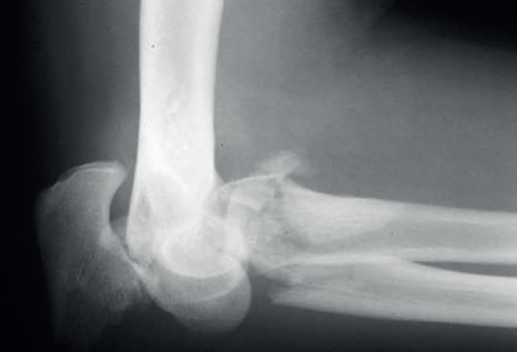

El siguiente patrón de inestabilidad tiene lugar tras una caída hacia atrás con el brazo extendido y provoca una inestabilidad en varo posteromedial. Se lesiona el LCL y se fractura la carilla anteromedial de la coronoides. En este tipo de lesiones, la cabeza radial típicamente no está fracturada.

Este tipo de lesiones se puede confundir con una fractura-luxación de Monteggia-Bado I. La diferencia es que no se ve afectada la articulación radiocubital proximal y los ligamentos colaterales medial y lateral permanecen anclados al fragmento distal del cúbito (Figuras 1, 2 y 3).